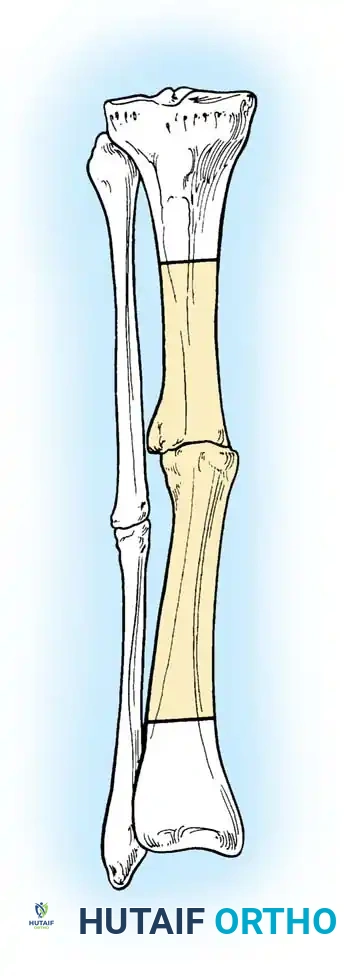

Diagrammatic representation of various hip fracture-dislocation patterns highlighting the relationship between the femoral head and acetabular rim.

Further classification of femoral head fractures associated with posterior hip dislocations, emphasizing the location of the fracture relative to the fovea capitis.